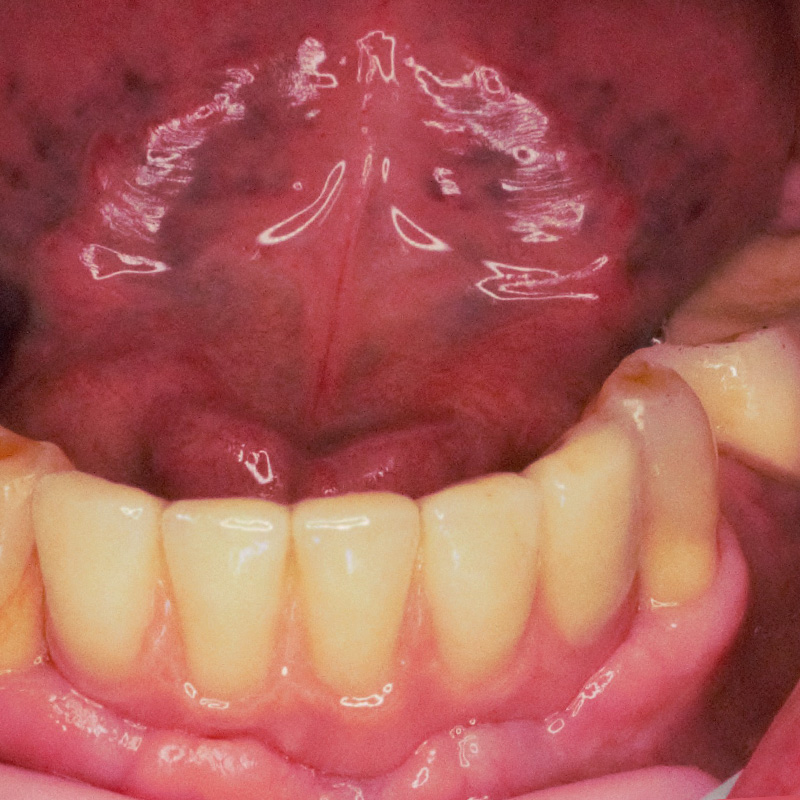

До и после лечения

К нам в клинику обратился пациент с жалобой на частично отсутствующие зубы на нижней челюсти.

После осмотра и предварительной диагностики врач Мельников Алексей Владимирович рекомендовал провести имплантацию с последующим протезированием металлокерамическими конструкциями. После согласования плана лечения с пациентом приступили к лечению.

В ходе лечения были проведены следующие работы:

- санация полости рта;

- установка 3 имплантов системы Alpha Bio;

- изготовление и установка металлокерамических коронок на имлантах системы Alpha Bio.